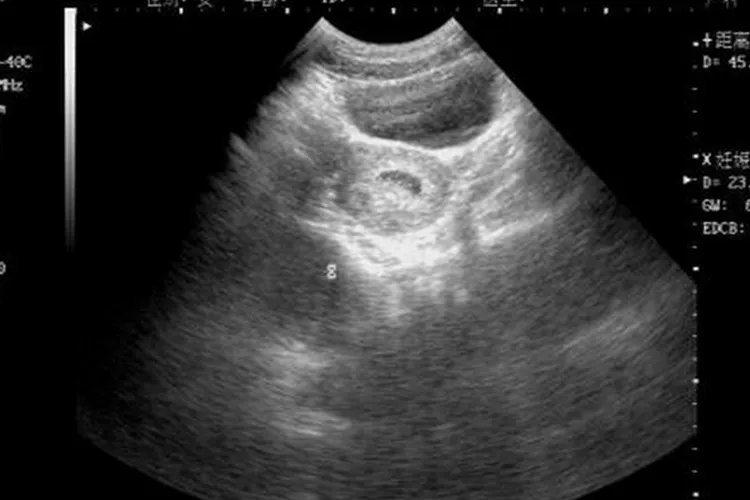

此外,孕期需要保证营养全面,同时建议定期B超检查,观察胎儿发育情况。